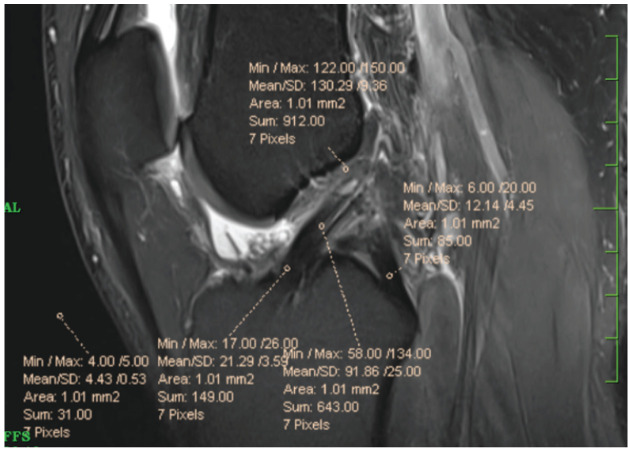

Materials and methods: In this case control study 15 patients undertaking ACL reconstruction with tripled peroneus augmented dHACM (G1) were prospectively monitored up for a period of 8 months along with 15 control patients (G2) without dHACM augmentation. Clinical and radiological outcomes were analysed and assessed about effect of augmenting the peroneus longus graft using dHACM. Clinical analysis included pre-operative two, four, six, and eight months post-operative Tegnor-Lysholm score, and radiological analysis included the 6th month postoperative MRI signal-to-noise ratio (SNR) measurements by mean signal-value at femoral insertion, midsubstance and tibial insertion of ACL graft.

Results: Clinically, as a mean Lysholm score of all patients, they were revealed to be consecutively high in G1 than in Group 2 at four, six, and eight months. The signal-to-noise ratio from the MRI results showed majority having good healing in G1 group.

Conclusions: Based on 6-month MRI, an effective ligamentization (SNR<75) was noticed in 53.33% of patients in the dHACM allograft enhanced group on comparison with 33% in the controls. The overall results show that the augmentation of dHACM allograft to ACL reconstruction yields in good patient outcomes at post-operative follow-up.